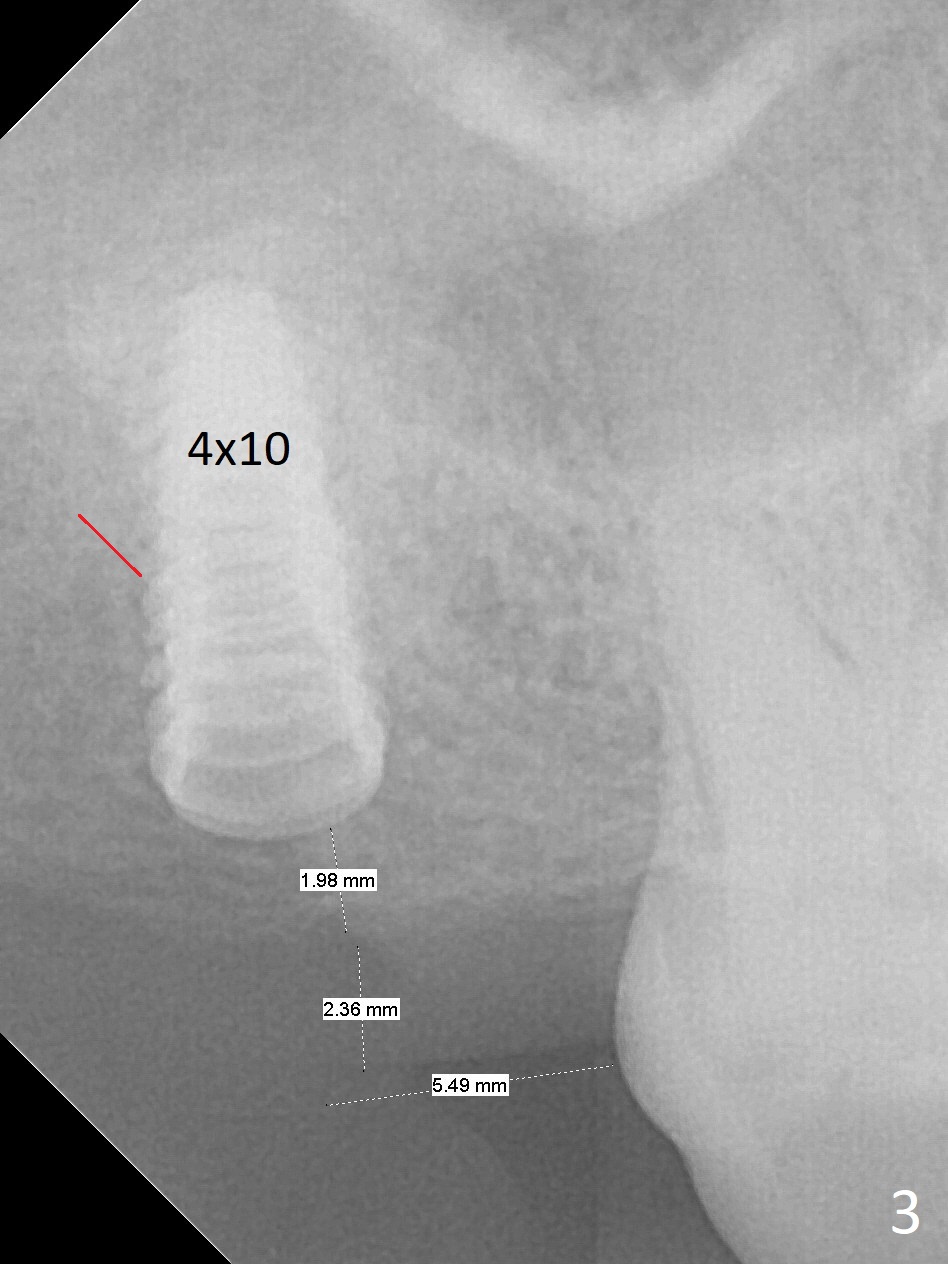

After extraction of the 3rd molar with mesial periodontal defect, osteotomy for 2nd molar implant is initiated in the mesial slope of the 3rd molar socket (Fig.1 red dashed line). When osteotomy is finished with IS drills and sinus lift with Magic Sinus Lifter (S-reamer with 11 mm stopper being short), a 4x10 mm dummy implant is placed with ~ 4 implant thread exposure (Fig.3). Following use of Lindamann bur to move osteotomy mesial and larger drill, a 4.5x10 mm implant is placed with 5-7 implant threads exposed distally (Fig.4,7 (~ 50 Ncm)). The bucco(B)-palatal(P) extent of the implant thread exposure is larger (Fig.5) than that associated with the 4 mm dummy implant (data not shown). The exposed implant surface is covered with Vera Graft (Fig.7*), Collagen plug and an immediate provisional after adjustment of abutment height (Fig.6,7). The bone density distal to the implant is low 3 months postop (Fig.8,9 CBCT) and 3.5 months postop (Fig.10,11). The permanent crown is cemented nearly 4 months postop. The distal cortical bone contacts the implant (Fig.12 ^), while the mesial bone increases in density (*) 2 years postop.